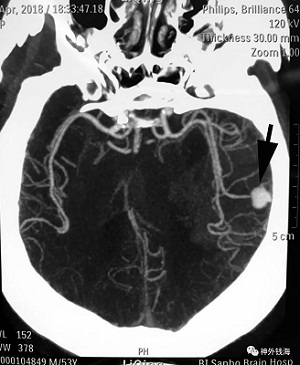

患者男性,53岁。主因“突发头痛6天”急诊由外院转入。意识清楚,双瞳孔无异常。言语不利,四肢可以活动。CT可见颅内出血,伴有大脑中动脉M3/M4段动脉瘤。

箭头所示为大脑中动脉远端动脉瘤,位于颅骨内板下方很近的位置。开颅需要小心,防止动脉瘤意外破裂。